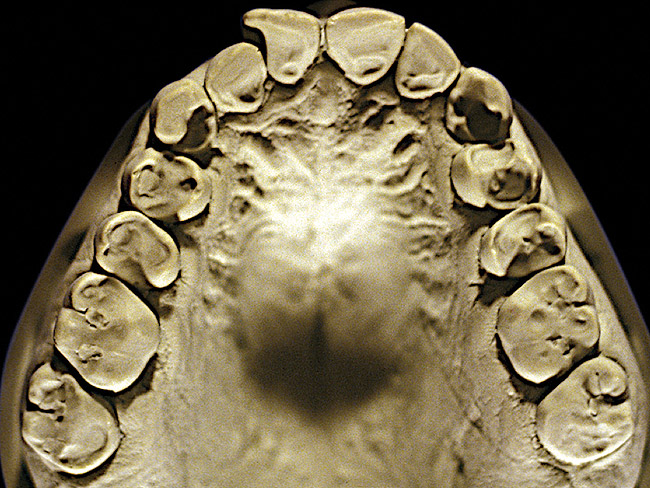

The patient shown in Figure 3 and Figure 4 exhibited severe NCLTS from bruxism. Examination of the casts indicated that the NCLTS was progressively greater toward the anterior teeth. Cupping and cratering was not present because there was no secondary cause. Figure 5 and Figure 6 detail another bruxism patient, but to a lesser degree and one with cupping/cratering caused by toothpaste. The cups or craters were not caused from bruxism because the teeth could not touch the bottom of the invaginations. In both featured patients, upon hand-articulating the casts, the NCLTS facets matched up and the diagnosis of bruxism was confirmed.

Figure 5  Moderate NCLTS from bruxism, maxillary arch.

Figure 5

Figure 6  Moderate NCLTS from bruxism, mandibular arch.

Figure 6